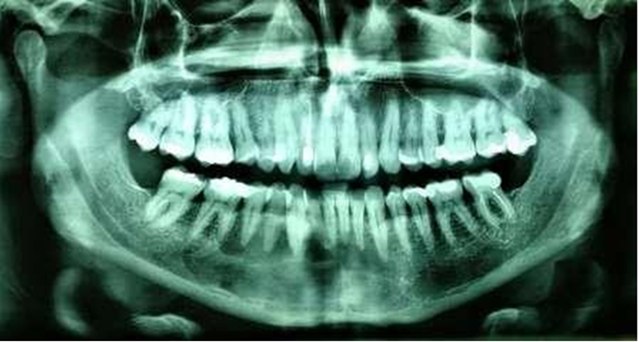

Figure 6. Radiographic appearance at 6 months post-op. There is an evident

radiographic sign of bone formation in the peripheral areas.

Figure 8. Radiographic examination at 4 years follow-up shows no signs of

recurrence.

Local irrigations and follow-ups were

maintained for 6 months, and a new radiographic examination was performed,

showing notable clinical and radiographic improvement, but still showing

radiolucency adjacent to neighboring teeth (Figure 6). At this time, it was decided to perform a new surgery

for enucleation and definitive treatment as shown in (Figure 7).